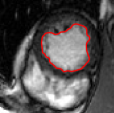

V-C LV and RV Segmentation: Quantitative Comparison to Commercial Software

We show experiments demonstrating the main use of our algorithm: in improving the prediction step of interactive segmentation methods. We show that less interaction is needed with our approach than a recent and widely used commercial cardiac segmentation software, Segment from Medviso [15, 44]. We perform quantitative assessment of the tracking performance of our method and compare it to Medviso. The evaluation was carried out on publicly available data sets, the MICCAI Left Ventricle Dataset [37] and the MICCAI Right Ventricle Dataset [25]. The validation dataset from [37] consists of 15 sets of cardiac cine-MRI images. Each set contains 6 to 20 2D slices from a 3D image, with each slice having 20 images of the cardiac phases. Similarly, the data set [25] contains 16 sets of cardiac cine-MRI images, each containing about 10 slices of 20 phases each. These data sets contain ground truth segmentations for left and right ventricles respectively (unfortunately ground truth for both the LV and RV is not available on a single dataset that we are aware of). Both methods start with the same initially correct segmentation, and subsequent frames are segmented via propagation. No manual interaction is used as we wish to show that our method would require less interaction. The regularity parameter in our method is found by choosing so that the results are closest to ground truth in a few training cases. The same parameter is then used for all other cases.

Figures 8 and 9 shows some sample tracking results of the proposed method and Medviso on full cardiac cycles of two different cases on both the LV dataset and the RV dataset. The ground truth (yellow) is superimposed when available. A summary of the results on the entire datasets is shown in Table I. The accuracy with respect to ground truth is measured using average perpendicular distance (APD) and dice metric (DM) for left ventricle, and Hausdorff distance (HD) and DM for the right ventricle. These metrics are chosen since they are the standard ones used on these datasets. Both qualitative and quantitative results show that our proposed method leads to more accurate segmentation of the ventricles and thus leads to less interaction than segmentation propagation schemes in than Medviso.